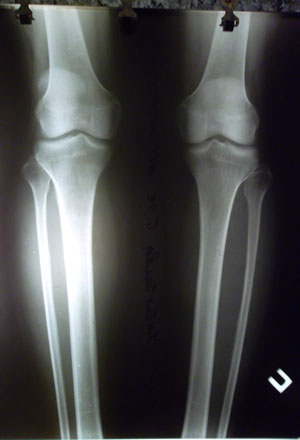

Процесс удлинения голеней и низведение головки малоберцовой кости. (уже 0,8 см)